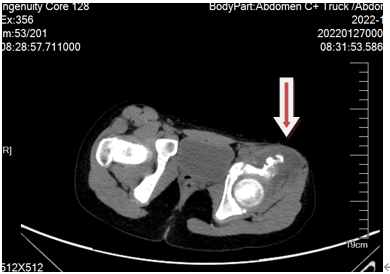

患者详情: 患儿1月余前无明显诱因下出现左侧髋关节疼痛,不伴发热及皮疹,行走困难,当地医院完善髋关节B超提示左侧髋部实性团状伴钙化,骨盆MRI提示左侧髂腰肌肿胀伴周围渗出灶,左髋关节少量积液。 影像: MRI示:左侧髂肌,髂腰明显肌肿胀伴信号异常:炎性改变?占位性改变?左股直肌及缝匠肌及左髂骨少许压脂高信号;左髋少许积液; 增强CT示:左侧髂腰肌至左大腿根部包块:占位(软骨来源?)?炎性改变?脉管畸形?其他? CT: 左侧髂腰肌至左大腿根部前群肌肉组织肿胀、肌间隙模糊不清,内见不规则稍低密度影子,病灶内可见斑片状致密影,临近髂骨皮质不光整,增强后可见不均匀轻中度强化,其内可见多发迂曲血管影。左侧髋关节内见少量积液影。 手术情况:术中诊断:左下肢皮下肿物:骨肉瘤?软骨肉瘤?见瘤体位于肌肉深处,包绕髋关节,内含鱼肉样组织,无明显包膜,于正常组织和瘤体的界限处钝性分离组织,电凝周围的滋养血管,见肿物浸润侵犯髂骨外侧,部分髂骨质地脆,表面呈虫蚀样改变,予刮除骨质表面异常组织,创面骨蜡止血。肉眼下切除大部分病灶组织。

影像学检查:(点击查看大图)